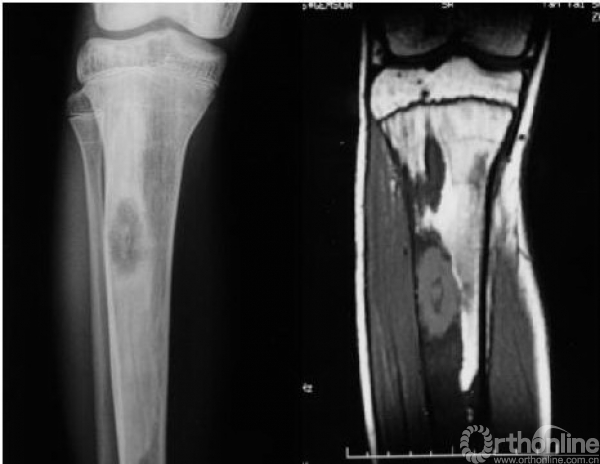

1、“磨砂玻璃状”改变:这是骨纤维异样增殖症最为常见的特征性X线表现(图5)

图5 左股骨呈“磨砂玻璃状”改变,看不到骨小梁,周围有硬化缘

2、囊状改变:在骨纤维异样增殖症中也比较常见(图6),其病理基础为肿瘤内有液化或出血,尤以股骨颈多见,表现为在磨砂玻璃的基础上出现单囊或多囊性膨胀透亮区。

图6 胫骨有明显的囊性变